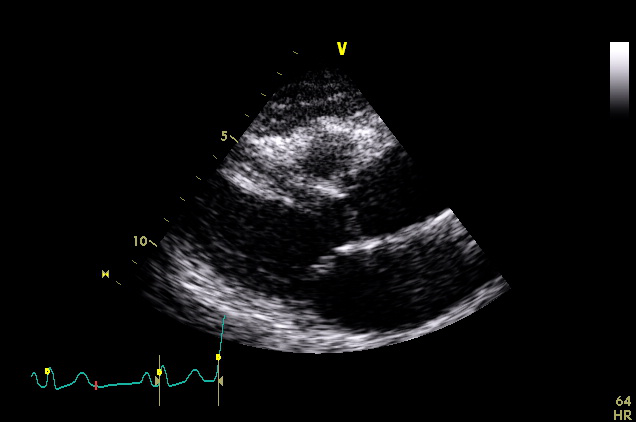

Subcostal & Suprasternal (3 views)

ImageView NameDescription

subcostal-heart subcostal-heart Subcostal window, focused on the heart